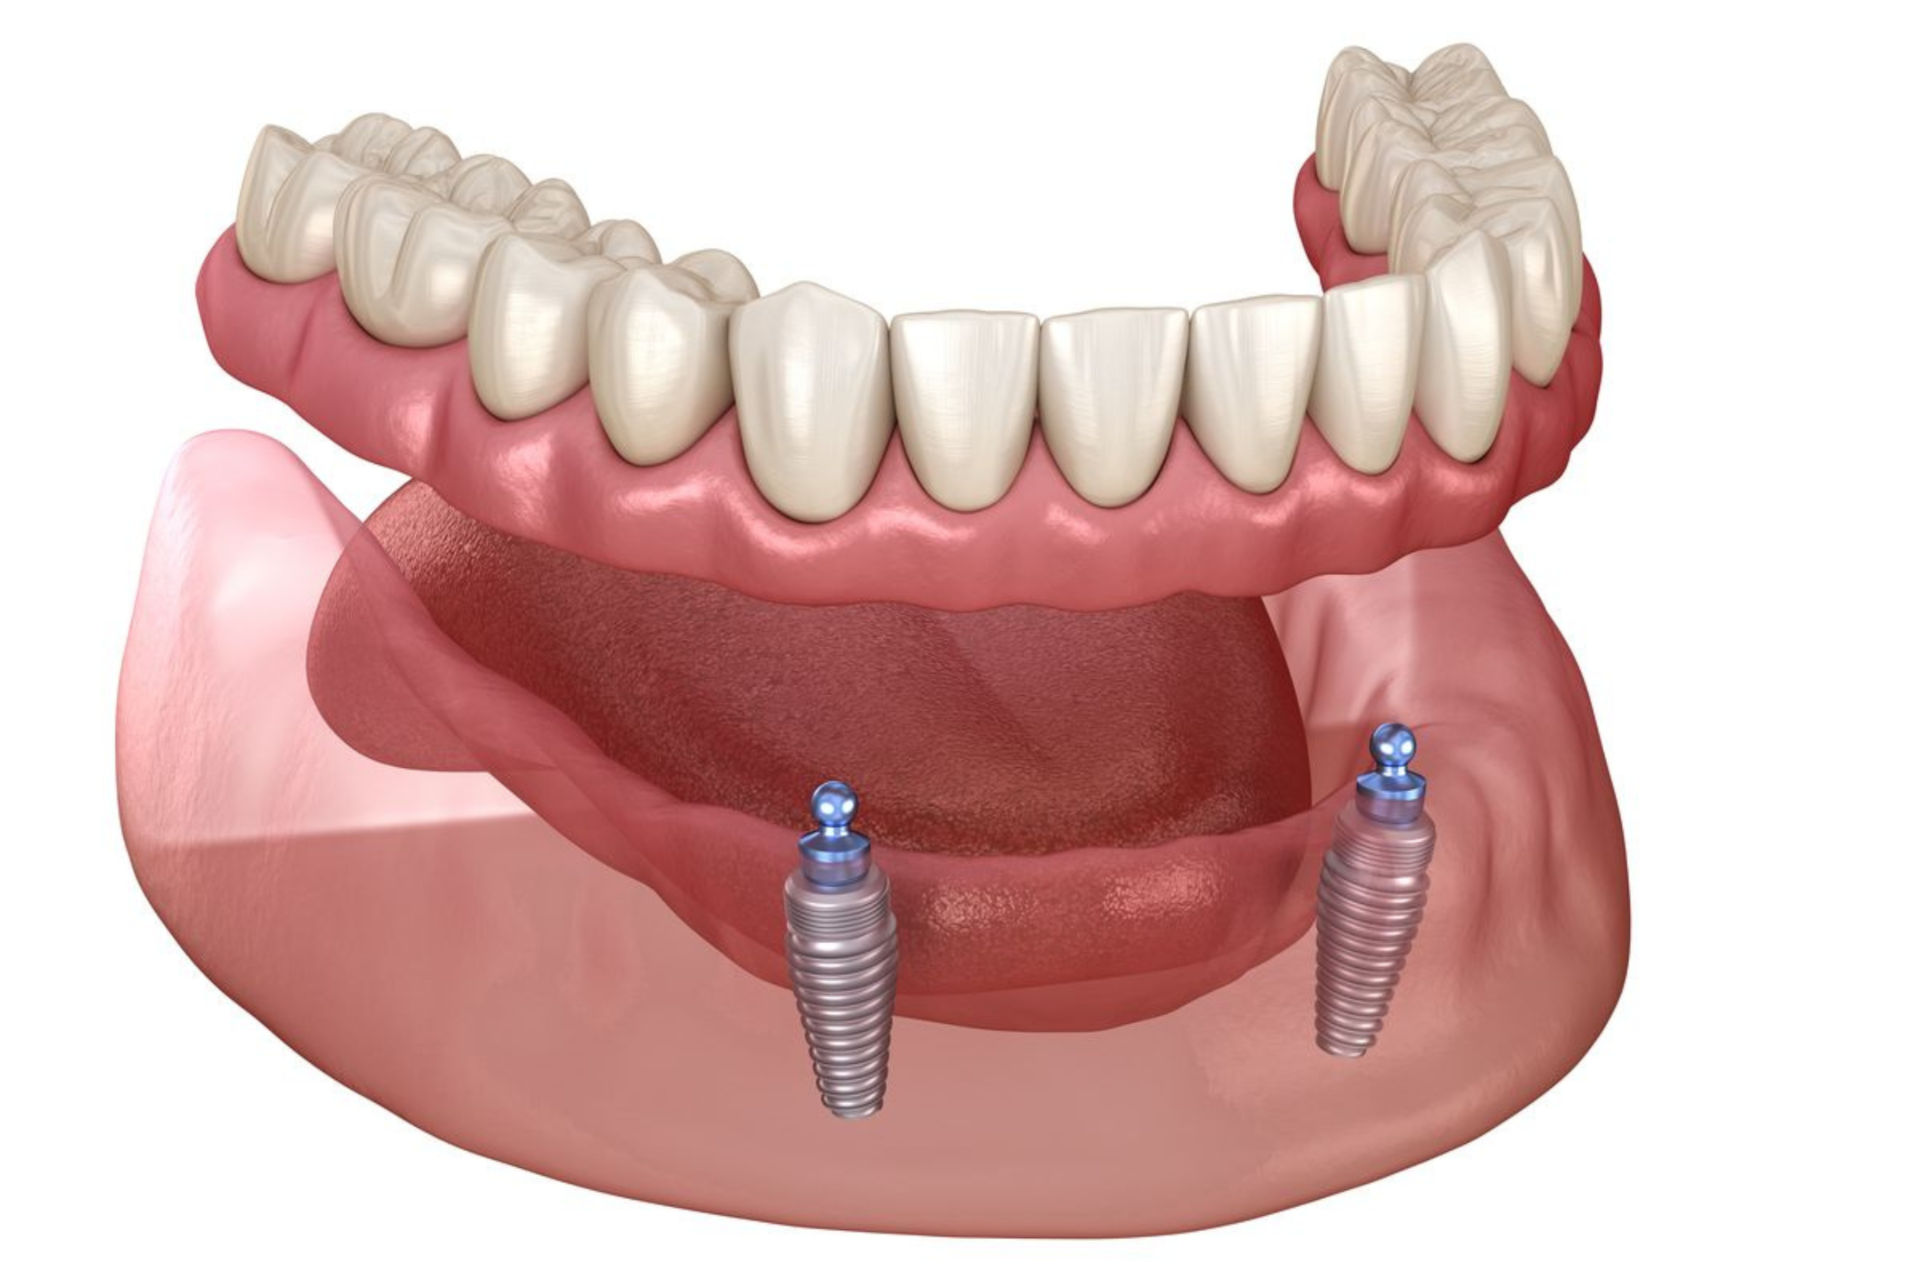

Locator-Prothese (auf 2 Implantaten)

Eine herausnehmbare Prothese, die auf zwei Implantaten stabil sitzt – eine sehr gute, kosteneffiziente Kompromisslösung für spürbar besseren Halt und Komfort.

ab 2.895 €

All-on-4

Eine festsitzende Komplettlösung für zahnlose Kiefer: 4 Implantate tragen eine stabile, ästhetische Brücke. Ideal für Patienten, die eine schnelle und zuverlässige Rundumversorgung wünschen – in vielen Fällen ohne zusätzlichen Knochenaufbau, bietet festen Biss, natürliche Optik und spürbar mehr Lebensqualität.

ab 6.963 €

All-on-6

Bei der All-on-6-Methode tragen 6 Implantate eine besonders stabile, festsitzende Brücke – ideal für Patienten, die maximale Haltbarkeit und Tragfähigkeit wünschen. Durch die größere Implantatanzahl entsteht eine noch robustere Basis.

ab 8.331 €

Stegprothese

Eine Stegprothese wird auf 4 Implantaten fixiert, die durch einen stabilen Steg verbunden sind. Sie bietet sehr festen, komfortablen und hygienischen Halt und kann zur Reinigung leicht herausgenommen werden – eine besonders praktische und zuverlässige Lösung.

ab 5.963 €

Stegprothese

Eine Stegprothese sitzt auf vier Implantaten, die mit einem stabilen Steg verbunden sind. Sie bietet einen sehr sicheren, bequemen und hygienischen Halt und lässt sich zur Reinigung einfach herausnehmen.

2.990 €